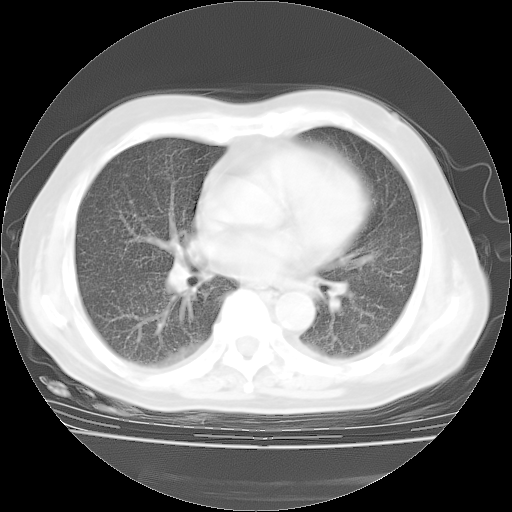

4月28日肺部CT——再次出现类似去年5月9日——透光度降低,“间质性”改变。

4月28日肺部CT——再次出现类似去年5月9日——磨玻璃样、间有“粟粒样”改变。

个人阅读4.14日肺部CT平扫:纵隔窗无异常,但肺窗示:双下肺内、后基底段有片絮状侵润影,部位以后基底段为著,以间质改变为主,呈急性肺泡炎征像,和首次住院影像学有相似之处。仅是个人读片,明日请相关专家再读片哈。其它建议同上。